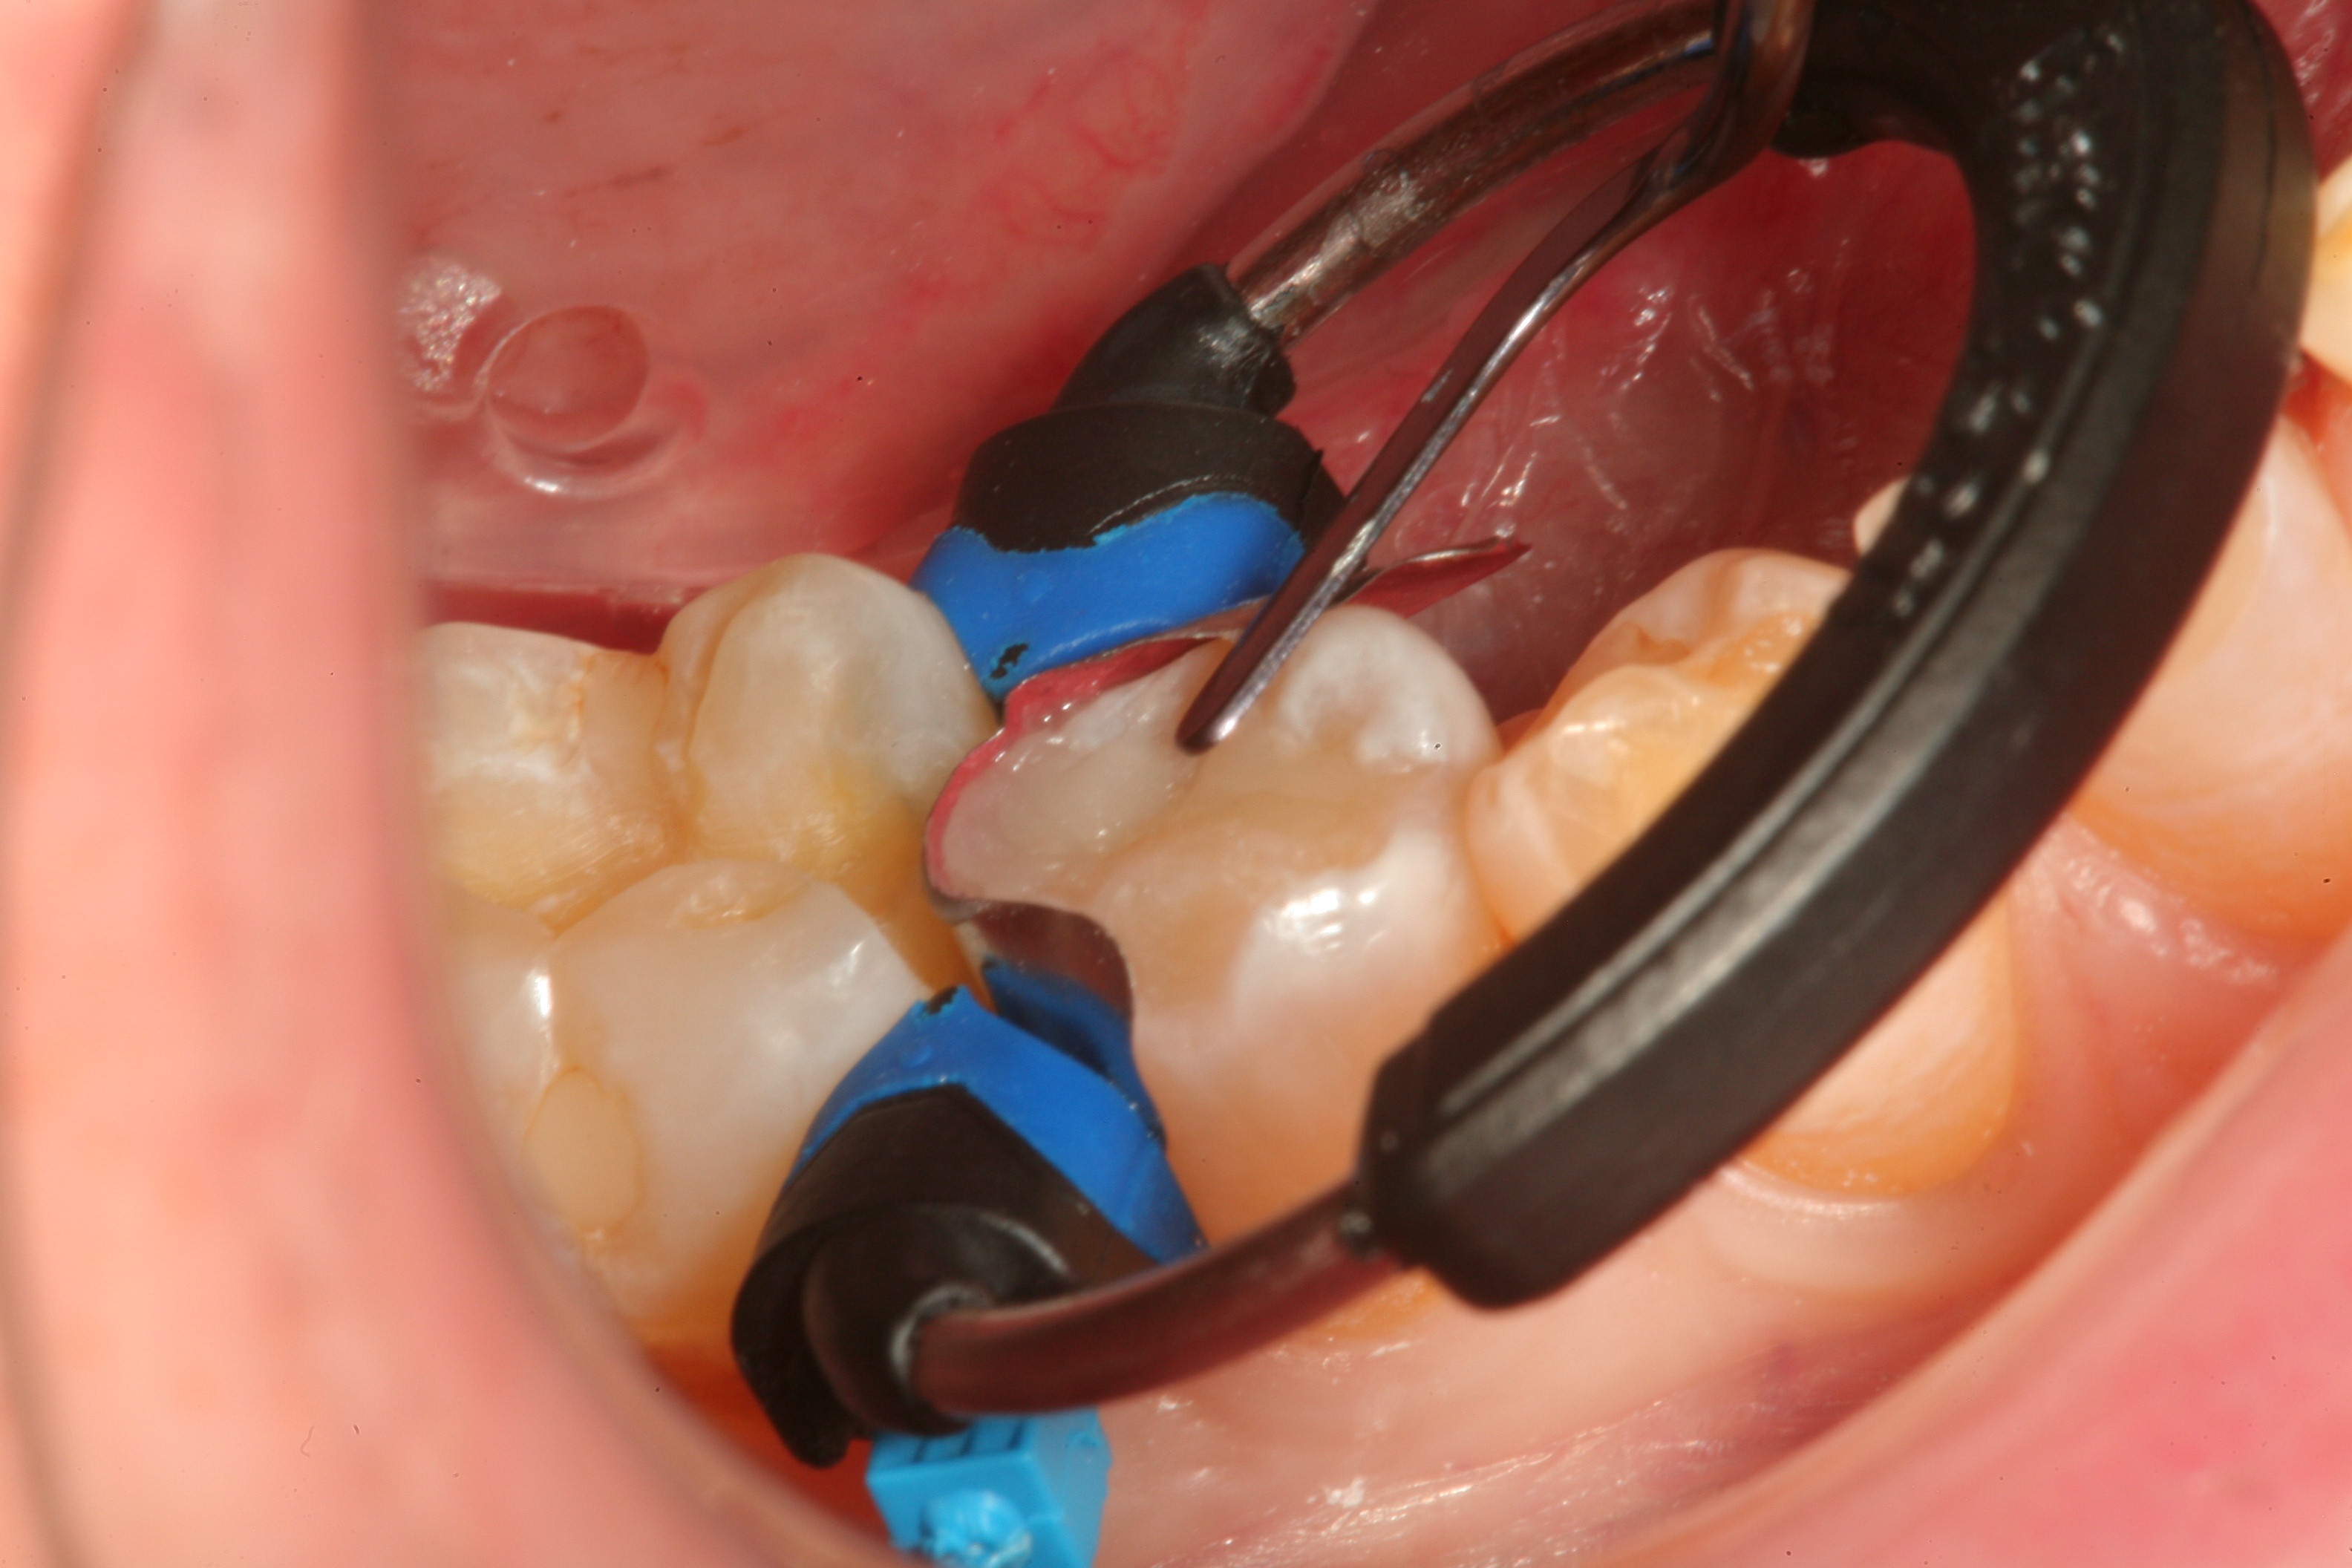

Fig 8. After isolation, a sectional matrix is placed to restore contact and proximal anatomic form to the composite to be placed. The goal is to perform as little rotary finishing and polishing as possible by having the matrix fit precisely to the cavity margins.

Figure 8